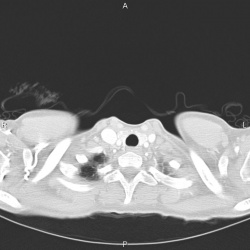

05.10.2015 - 19:00

Мужчина 1934 г.р. поступил по скорой с ишемическим инсультом. На рентгенограмме расширенная тень сердца.

Подскажите что в средостении?